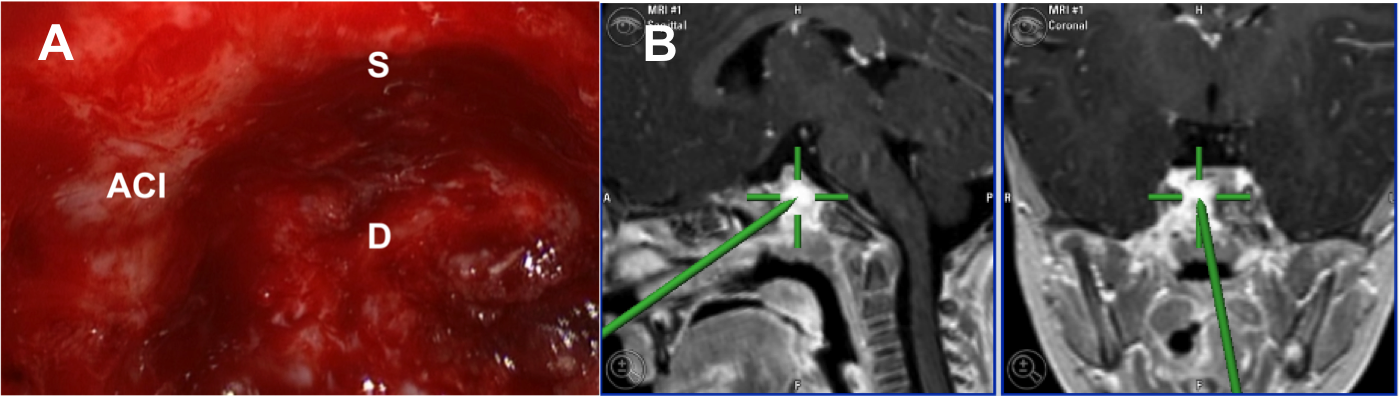

Resultados: Fueron intervenidos 8 pacientes entre los 2 y 14 años, con una edad promedio de nueve años y un seguimiento promedio de 16 meses. En el 75% se hizo una resección total del tumor. Un paciente requirió una reintervención y un paciente fue sometido a radiocirugía post-operatoria. 1 paciente falleció a pesar de múltiples intervenciones, quimioterapia y radioterapia.